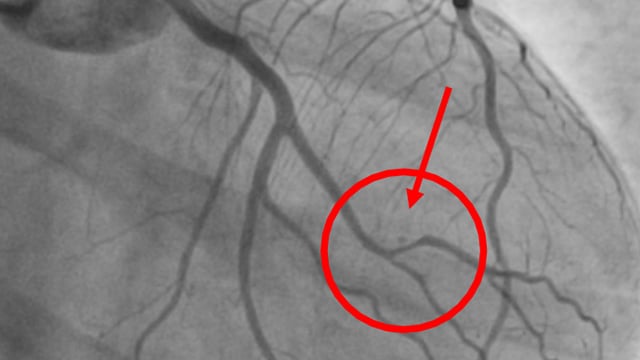

This session explores complex coronary challenges and anatomical anomalies encountered in clinical practice. Topics include management of thrombus showers from unexpected culprits, ultra-low contrast angioplasty in mesenteric ischemia, advanced bifurcation PCI techniques with IVUS guidance, and troubleshooting difficult stent delivery scenarios in calcified lesions and challenging...